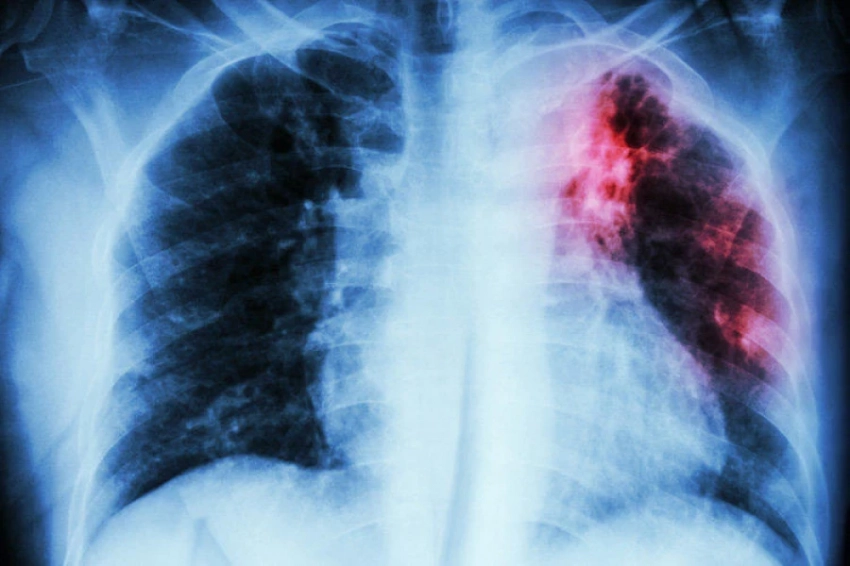

Кыргызстанда туберкулез менен инфекциялануунун белгилери жана тобокелдиктери жөнүндө адистер эскертишти

Кыргызстандагы саламаттыкты сактоо жана массалык маалымат каражаттарын күчөтүү боюнча республикалык борбордун маалыматына ылайык, Кыргызстанда көптөгөн адамдар туберкулез бактериясы менен жуктуруп алган, бирок алардын болгону 5-10% туберкулез менен оорукканга жетишет. Дүйнө жүзүндө үч кишинин бири бул микроорганизмдин taşıyıcısı, бирок иммундук система анын көбөйүшүн басып туруу мүмкүнчүлүгүнө ээ.

Статистикага ылайык, туберкулез (ТБ) менен диагноз коюлган бардык учурлардын жарымынан көбү 18ден 44 жашка чейинки адамдар арасында катталууда, бул эмгекке жөндөмдүү калкка таандык.

«Медициналык кызматкер сизге мокрота анализин өткөрүү, флюорография же кеудөнүн рентгенин жасоо сунуштай алат, балдар үчүн — Манту сынагы. Специалистке эрте кайрылуу жана туберкулезду тез аныктоо ийгиликтүү дарылануу жана мурдагы жашоо образына кайтуу мүмкүнчүлүгүн жогорулатат»,- деп белгиленет РЦУЗдан.